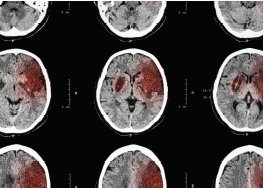

A lower-than-standard dose of intravenous alteplase (Activase; Genentech) for the treatment of patients with acute ischemic stroke is noninferior to the standard dose and is associated with significantly reduced risk of intracerebral hemorrhage, according to new study findings.

Secondary outcomes of the study showed that significantly more patients in the standard dose group experienced a major symptomatic intracerebral hemorrhage compared with those in the low-dose group (2.1% vs 1.0%, P = .01). In addition, significantly more patients in the standard-dose group had a fatal event within 7 days (1.5% vs 0.5%, P = .01). No significant differences were seen in 90-day mortality between the 2 groups (10.3% vs 8.5%, respectively, P = .07).

The study’s findings suggest that alteplase 0.6 mg/kg may be associated with a reduced risk of intracerebral hemorrhage compared with alteplase 0.9 mg/kg.